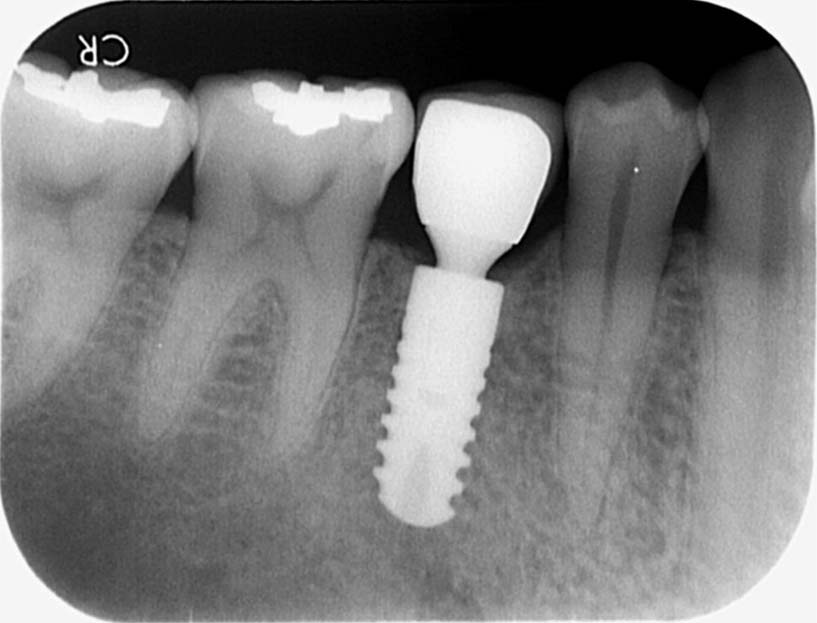

- 植牙—將植體植入牙床內,約3~6個月後,等待骨細胞和植體產生骨整合。

- 置入支檯齒—植體和骨頭產生骨整合後,挑選適合牙齒咬合的支檯齒,然後委由專業的牙技師製作假牙。

- 裝上假牙—假牙製作完成後,利用螺絲或黏合方式固定假牙,並調整咬合。